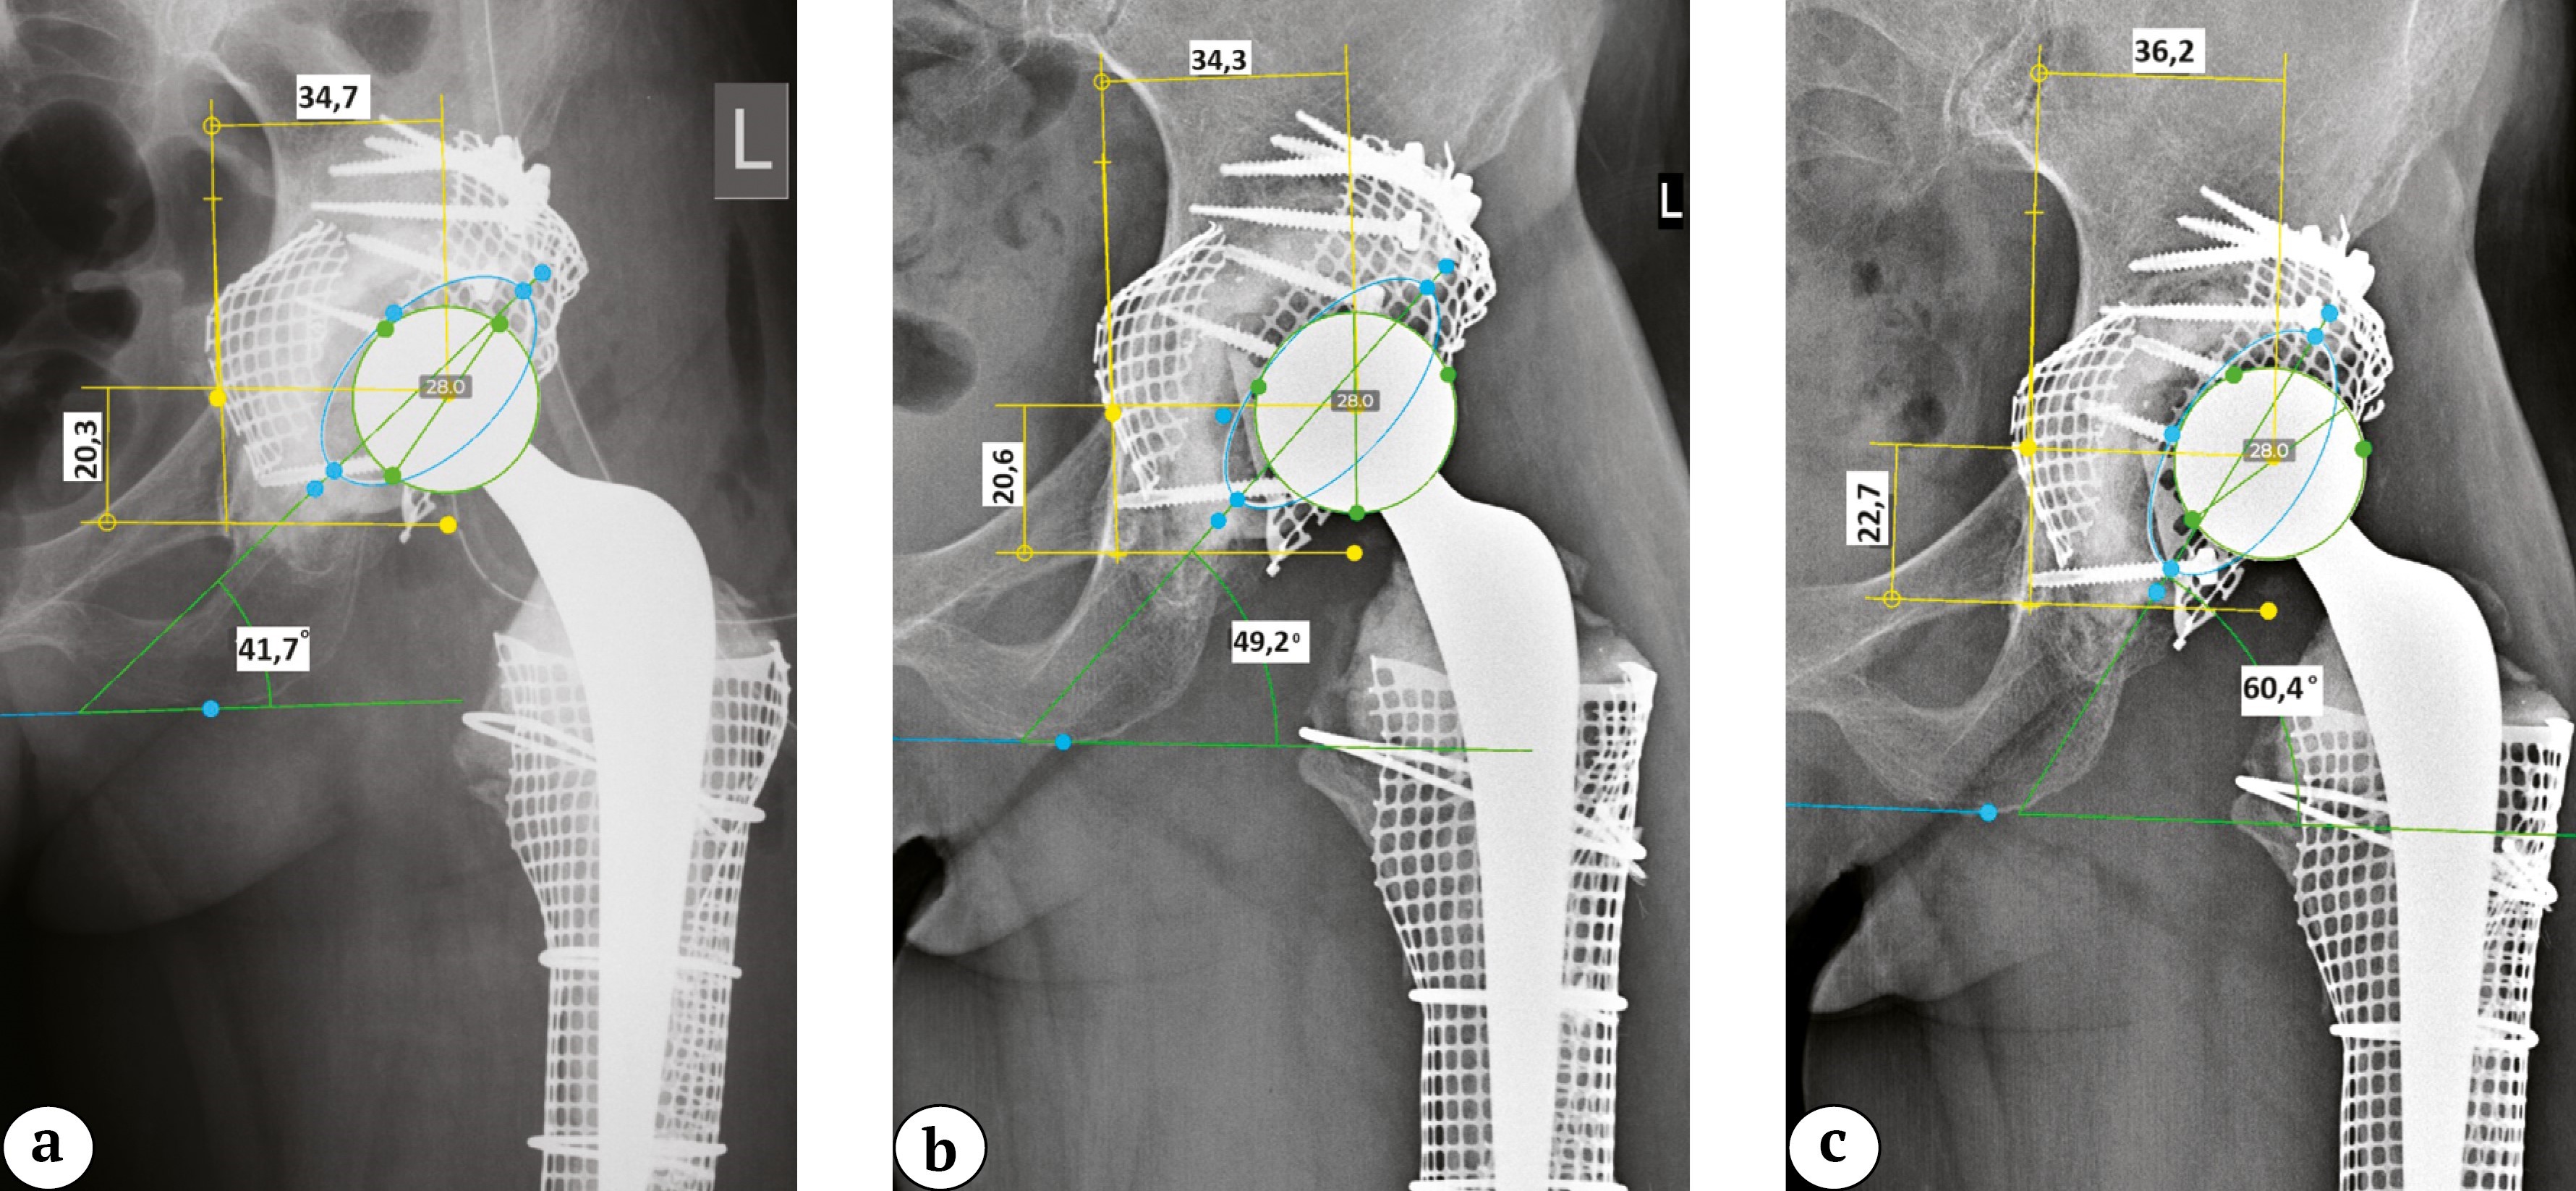

Уплотнение материала и уменьшение его объема при увеличении числа циклов нагрузки можно пояснить клиническими примерами. Проведена оценка результатов рентгенологического исследования в динамике у пациентки 59 лет (пациент 1), перенесшей двухэтапное ревизионное эндопротезирование по поводу инфицированной нестабильности компонентов эндопротеза с использованием ИКП на заключительном этапе (рис. 6). Для анализа динамики миграции тазового компонента выбраны обзорные рентгенограммы таза, полученные непосредственно после операции, через 3 года после оперативного вмешательства и на последнем контрольном осмотре через 7 лет (рис. 7). Абсолютные значения представлены в таблице 3.

Рис. 7. Клинический пример миграции тазового компонента у пациента 1 без развития расшатывания: a — после операции; b — через 3 года; c — через 7 лет (смещение проксимально и латерально, увеличение инклинации и изменение антеверсии)

Figure 7. Clinical example of the pelvic component migration in patient 1 without subsequent loosening: a — after surgery; b — in 3 years; c — in 7 years (proximal and lateral displacement, increased inclination, change in anteversion)

Таблица 3

Показатели позиции тазового компонента эндопротеза левого тазобедренного сустава у пациента 1 на различных сроках наблюдения

Показатель | После операции | Через 3 года | Через 7 лет | Δ |

Расположение центра ротации по оси Y, мм | 20,3 | 20,6 | 22,7 | 2,4 |

Расположение центра ротации по оси X, мм | 34,7 | 34,3 | 36,2 | 1,5 |

Инклинация, град. | 41,7 | 49,2 | 60,4 | 18,7 |

Антеверсия, град. | 34,0 | 27,8 | 30,8 | 3,2 |

В динамике спустя 7 лет отмечается смещение центра ротации в большей степени в краниальном направлении, увеличение инклинации тазового компонента и изменение угла антеверсии. При этом классических рентгенологических признаков расшатывания тазового компонента по Charnley в виде рентгенопрозрачных линий на границе интерфейсов кость – цемент не выявлено. Клиническая оценка функционального результата по модифицированной шкале HHS на момент последнего клинического осмотра составила 97 баллов.